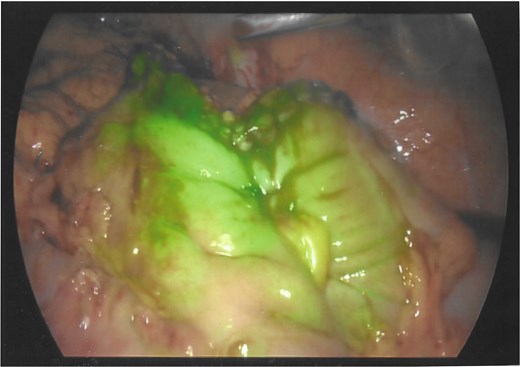

The wound healed well post-operatively. The patient returned for planned excision of remaining fistula (Fig. 3) and primary closure of the skin. Her postoperative follow-up remains unremarkable with no further wound complications.